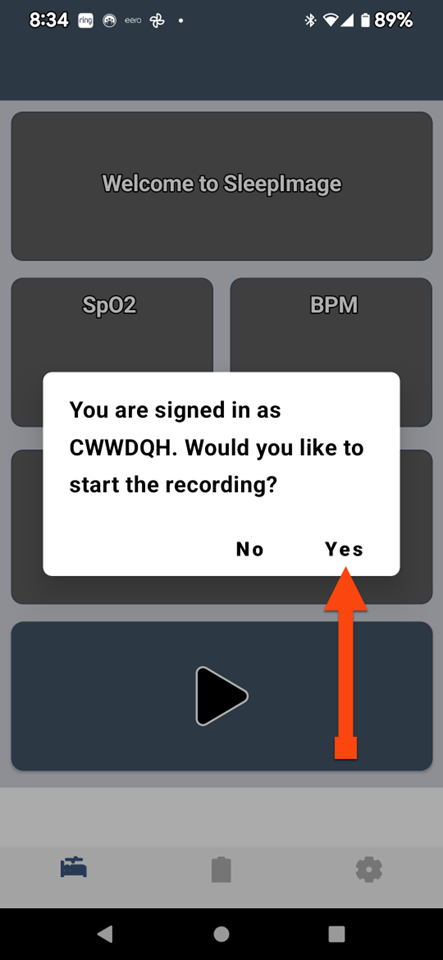

SLEEPIMAGE APP (Android)

SLEEPIMAGE APP (Android)

SLEEPIMAGE APP (Android)

SLEEPIMAGE APP (Android)

SLEEPIMAGE APP (Android)

SLEEPIMAGE APP (Android)

SLEEPIMAGE APP (Android)

SLEEPIMAGE APP (Android)

SLEEPIMAGE APP (Android)

SLEEPIMAGE APP (Android)

SLEEPIMAGE APP (Android)

SLEEPIMAGE APP (Android)

SLEEPIMAGE APP (Android)

SLEEPIMAGE APP (Android)

SLEEPIMAGE APP (Android)

SLEEPIMAGE APP (Android)

SLEEPIMAGE APP (Android)

SLEEPIMAGE APP (Android)

SLEEPIMAGE APP (Android)

SLEEPIMAGE APP (Android)

SLEEPIMAGE APP (iPhone)

SLEEPIMAGE APP (Android)

SLEEPIMAGE APP (Android)

SLEEPIMAGE APP (Android)

SLEEPIMAGE APP (Android)

SLEEPIMAGE APP (Android)

SLEEPIMAGE APP (Android)

SLEEPIMAGE APP (Android)

SLEEPIMAGE APP (Android)